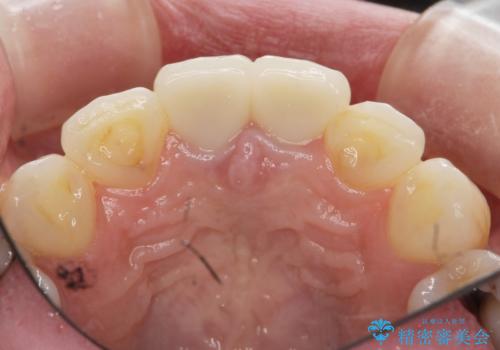

前歯が疼く セラミッククラウンのやり替え

- 「幼少期に転んで治療した前歯がうずく、疲れると膿が出る。」と治療を希望され来院されました。

X線写真検査に加え圧痛、打診痛が認められたため、慢性根尖性歯周炎と診断し、根管治療から行うセラミック治療を計画します。

今回は根尖性歯周炎に対する根管治療を行ったことで症状は改善し、快適に食事ができる状態へと改善しました。